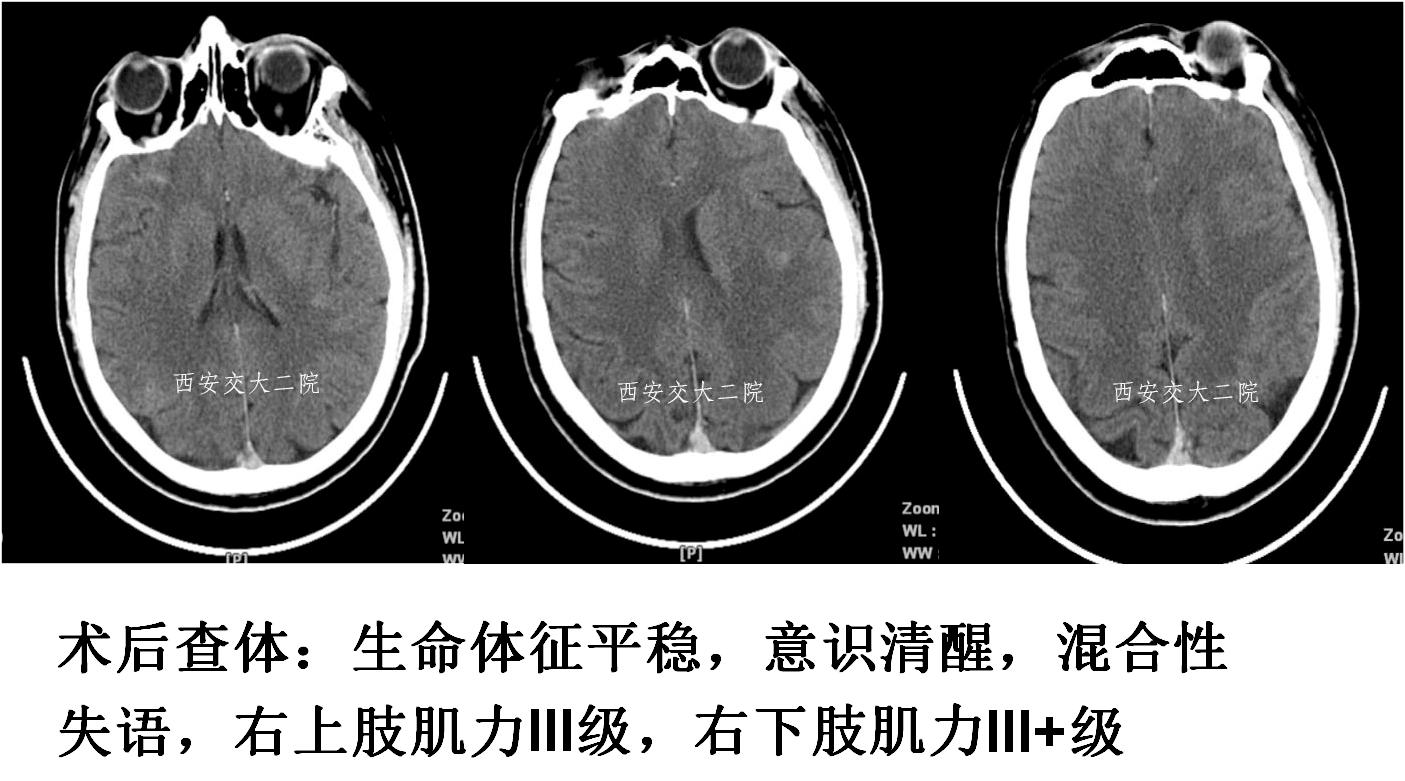

取栓后即刻脑CT及临表

术后24h脑CT及临表

术后4天脑CT及临表

术后2周脑CT及临表